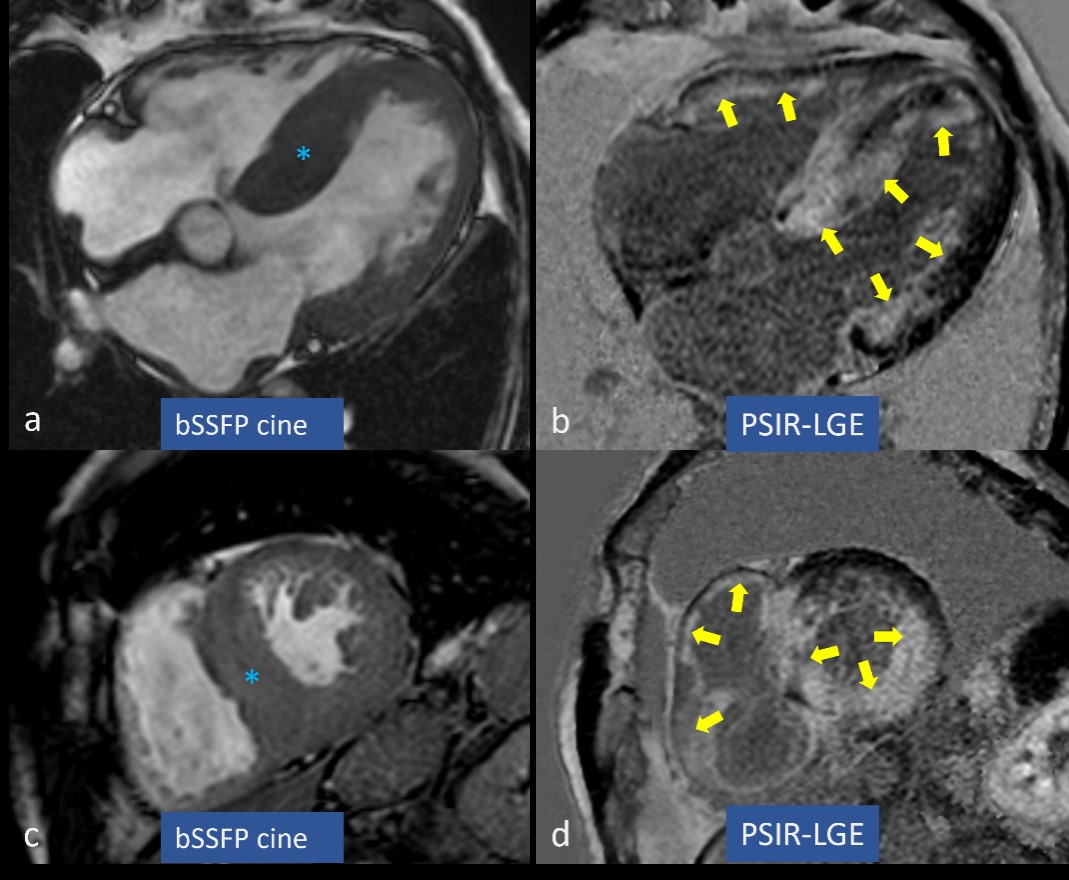

Typical MRI features of CA are: concentric left ventricle hypertrophy (Figs. 1a,b,2a,c) often associated with atrial walls thickening (Fig. 1a); restrictive configuration of the heart characterized by large atria, small ventricles, and reduced longitudinal shortening of the LV; global, circumferential subendocardial LGE (Figs. 1c,e,f,g,2b,d) defined “subendocardial tramline” or “zebra-pattern” with a non-coronary distribution; blurry, inhomogeneous suppression of myocardial signal and dark blood pool on LGE; atrial LGE (Fig. 1e,f); very high global native myocardial T1 values (Fig. 1d) and high ECV (Fig. 1h); pleural and pericardial effusions [29].

Fig. 2.

Fig. 2.Left ventricular hypertrophy and late gadolinium enhancement (LGE) in cardiac amyloidosis (CA). Concentric left ventricular hypertrophy is marked by blue asterisks in (a,c), while circumferential subendocardial and partially transmural LGE is highlighted by yellow arrows in (b,d). bSSFP, balanced steady state free precession; PSIR, phase sensitive inversion recovery.